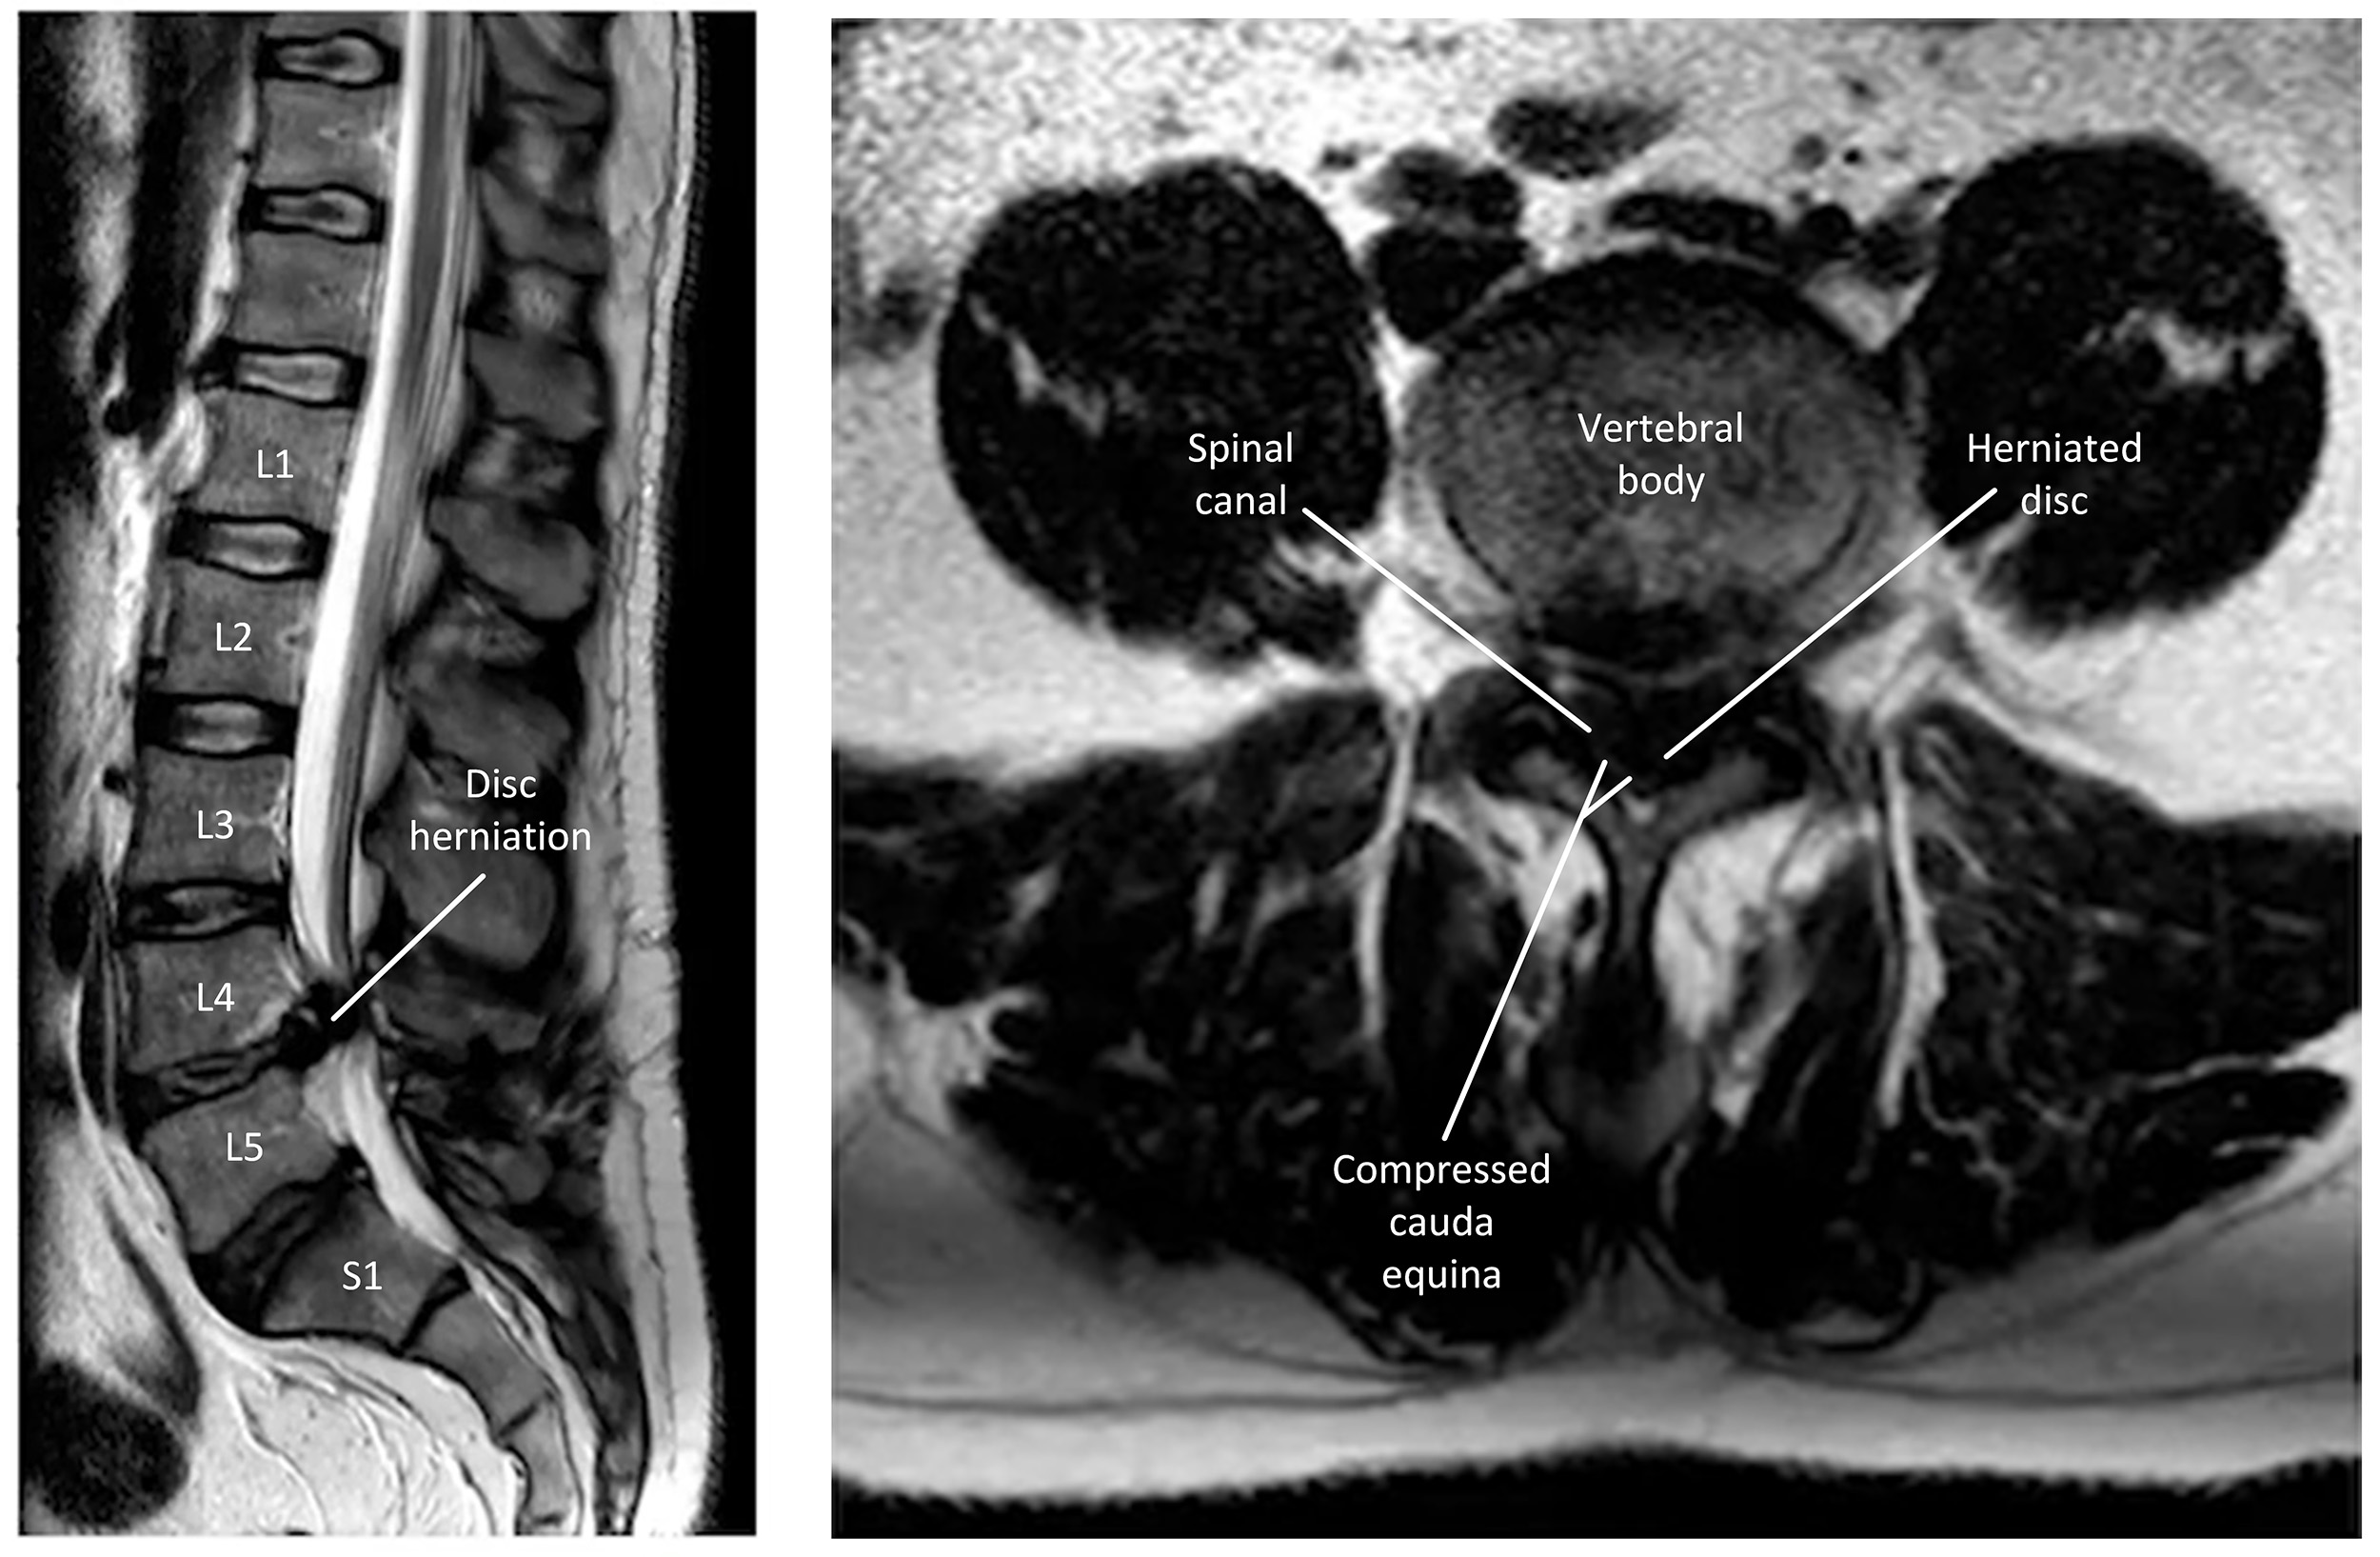

CES is caused by compression of the nerve roots within the spinal canal (Fig. 2). It occurs in 3% of disc herniations [21], which accounts for 45% of CES cases [22]. This compression arises from a disc herniation at the L4/L5 or L5/S1 level [23]. Those with lumbar stenosis are predisposed to CES upon disk herniation owing to a narrower spinal canal [24]. The most common causes of CES are listed in Table 1 (Ref. [21]) below.

Fig. 2.

T2 weighted magnetic resonance images of cauda equina syndrome (CES). The left sagittal image shows L4 disc herniation leading to compression of the cauda equina. The right axial image shows the L4 disc occupying the space within the vertebral canal, compressing the cauda equina. The image does not contain any identifiable patient data, therefore informed consent is not required.